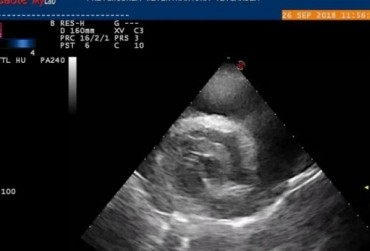

Obraz echo serca przez zabiegiem usunięcia worka osierdziowego 1

19 lutego 2019

Rafał Kraszewski